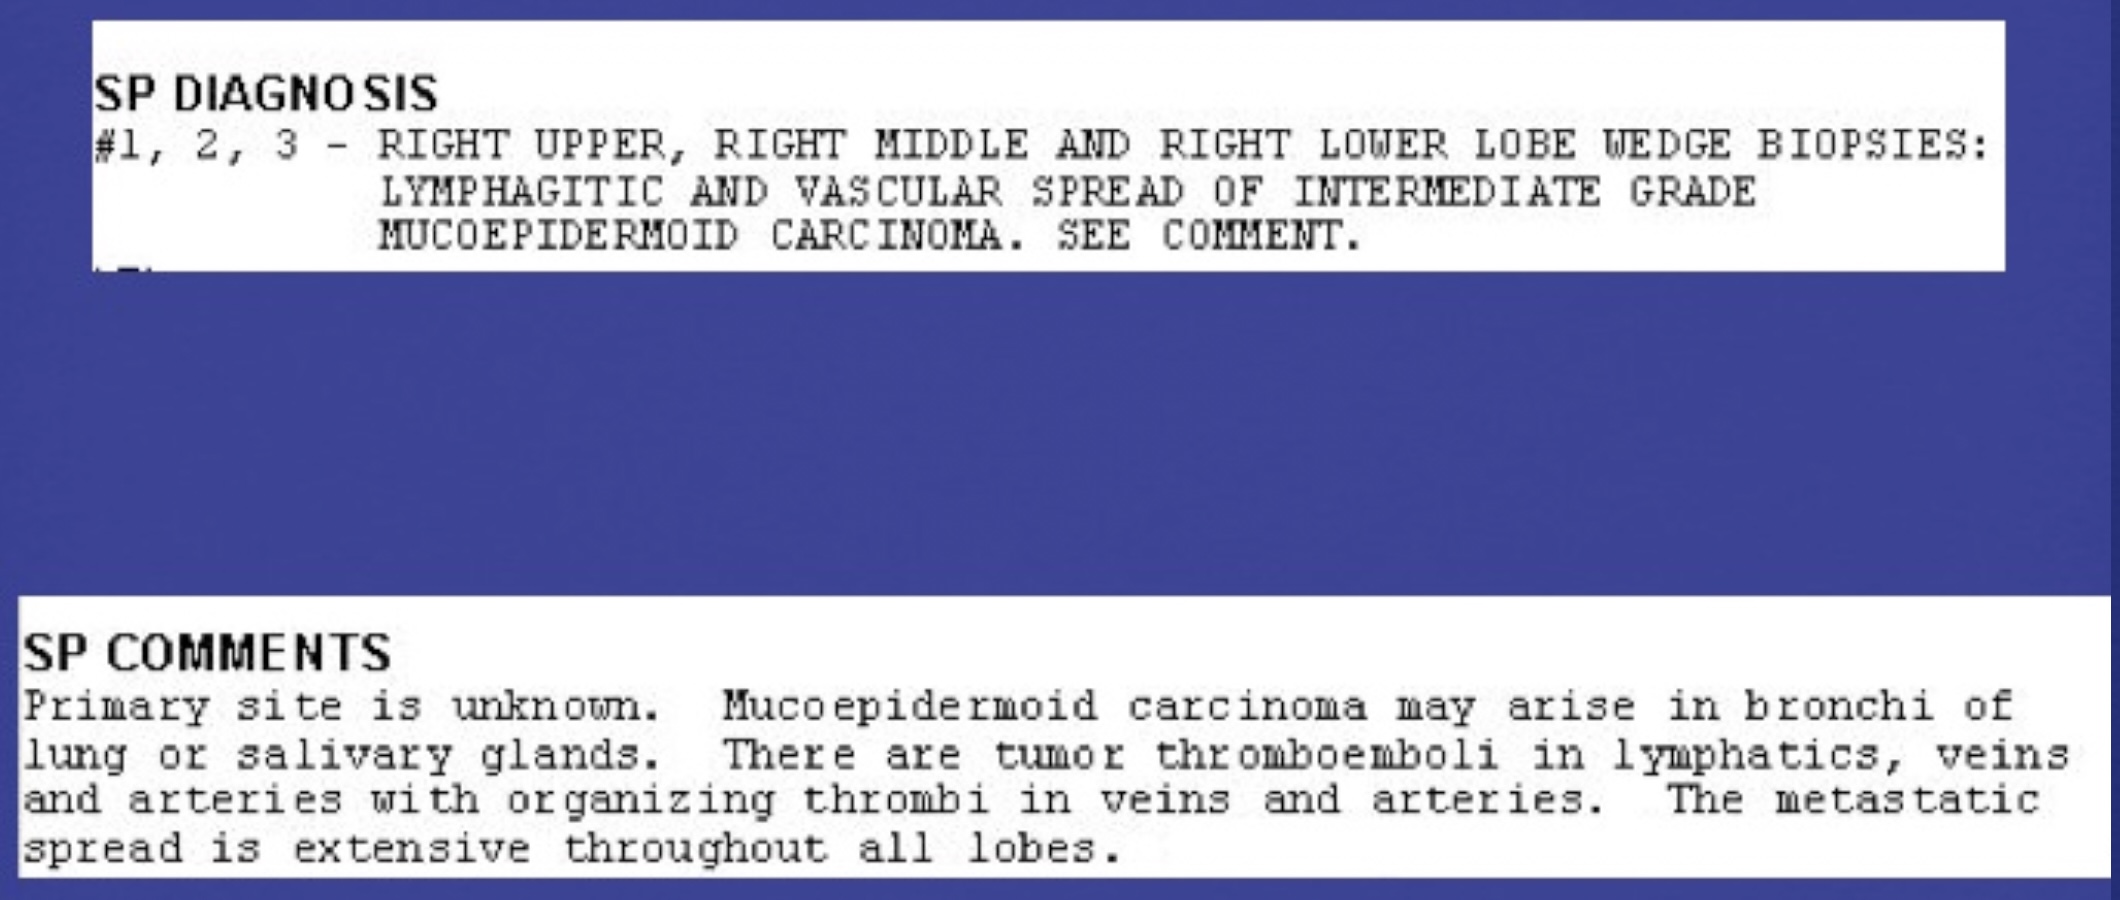

Lung Edema from Impaired Clearance of Lung Water. Role of Lymphatics.

- lymph flow easily clears physiologically filtered lung water

- lymphatic obstruction, typically by metastatic tumor–lymphangitic tumor spread–manifests as lung edema

- the edema is typically interstitial, may be focal and asymmetric, and associated with transudative pleural effusions

- lymphangitic tumor spread may be accompanied by other forms of metastases, such as solid nodules

- uncommonly, lymphangitic tumor spread is the first manifestation of cancer

Unexplained, new dyspnea in a healthy female